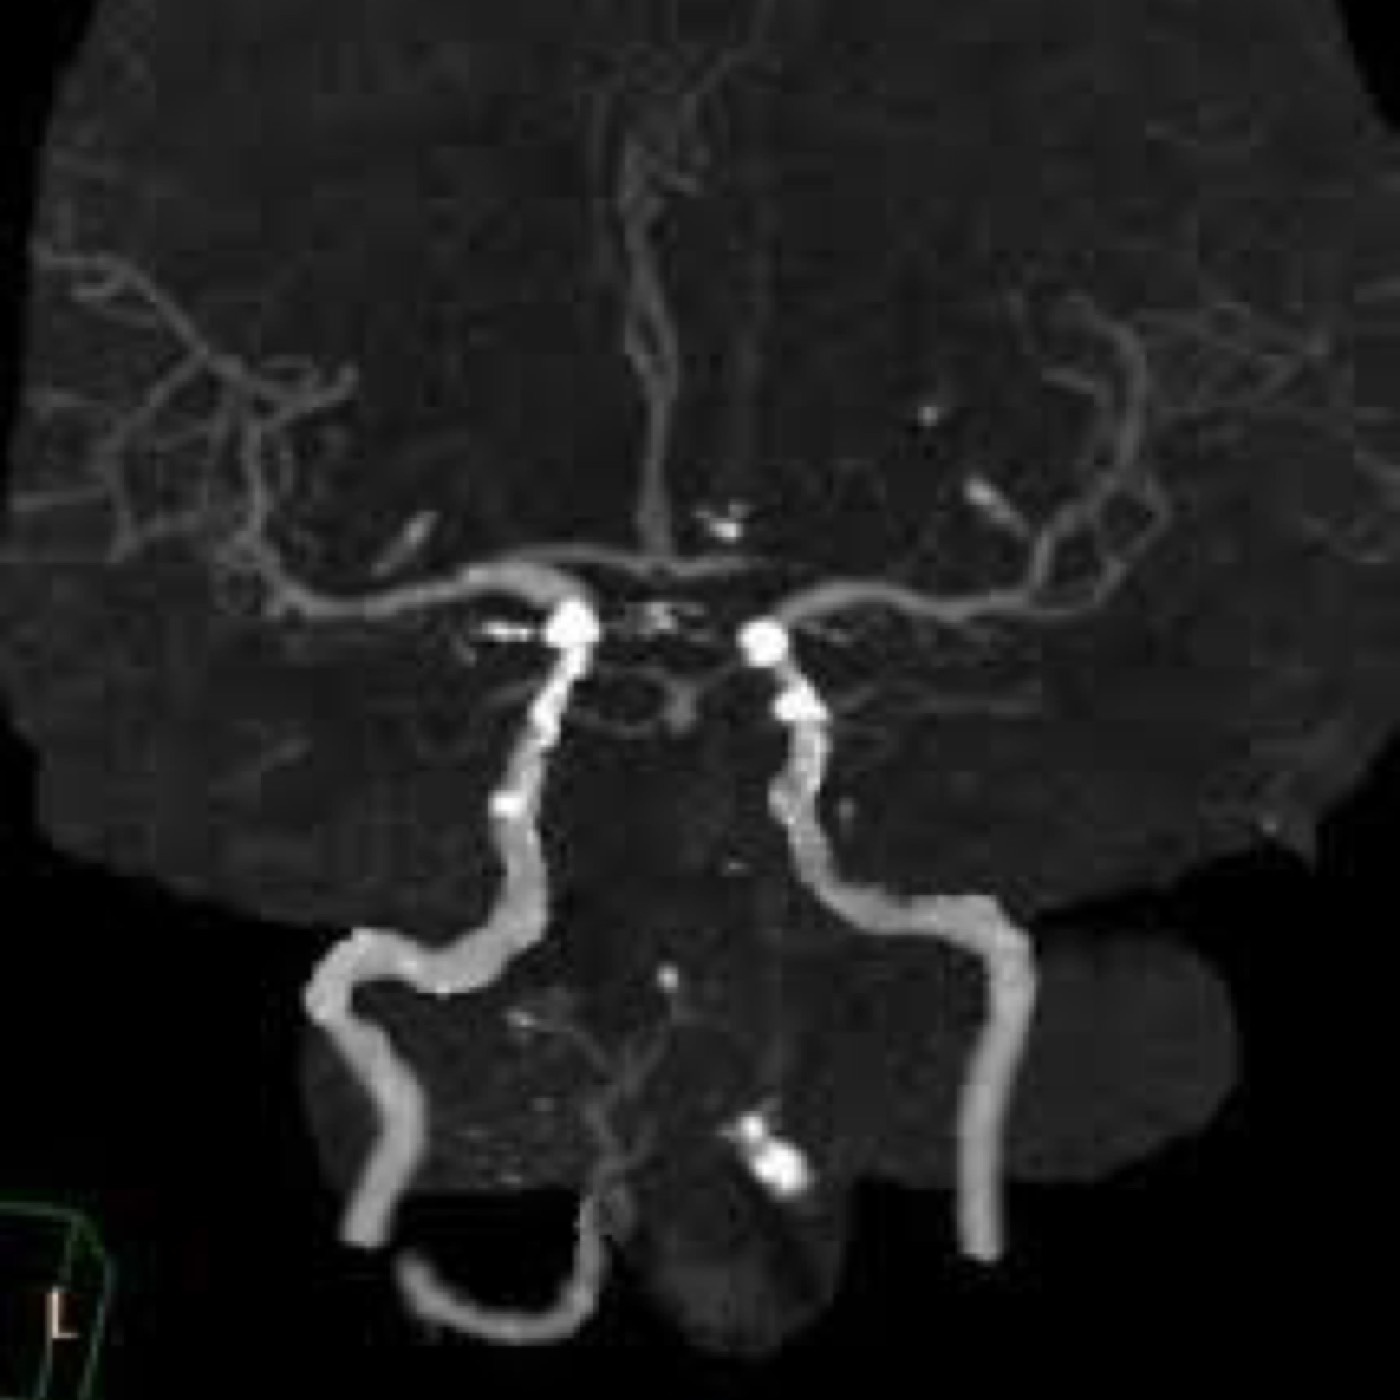

Contributors: Travis Barlock MD, Jeffrey Olson MS4 Feel free to use the cases below for your own practice. All of the scenarios are completely made up and designed to hit several teaching points. Case 1 25 M, presents to the ED with chest pain. Stabbing, started a few hours ago, substernal. Thinks it is GERD. After 2-3 minutes, pain worsens and radiates to the back. VS: BP 125/50 (Right arm 190/110). HR 120. RR of 18. Sat 98% on RA. Additional VS: Temp of 37.2, height of 6'5", BMI of 18. PMH: None, doesn't see a doctor. Meds: None FH: Weird heart thing (Mitral Valve Prolapse), weird lung thing (spontaneous pneumothorax), tall family members with long fingers and toes Physical Exam: Cards: Diastolic decrescendo at the RUSB, diminished S2. UE pulses are asymmetric, LE pulses are asymmetric, carotid pulses are asymmetric, BP is asymmetric MSK: Knees, elbows, and wrists are hypermobile. Imaging: CXR #1 normal, #2 widened mediastinum (no read yet but shows widened mediastinum), POCUS shows small effusion CTA/MRA doesn't come back until after the case. ECG: Sinus Tach Labs: NT-proBNP 500 pg/mL D-Dimer: 7000 ng/L CBC: Hemoglobin: 13.5 g/dL, WBC: 20,000/µL, Platelets: 250,000/µL Chem 7: Na 138, K, 5.7, Cl 102, Bicarb 17, BUN 45, Creatinine: 3.5 mg/dL, Glucose: 180 LFTs: Albumin 2.4, Total protein 5.5, ALP: 140, AST: 3500, ALT: 2800, TBili: 3.2, DirectBili: 2.4, Ca: 7.8 LDH: 2200 PT: 20.5, INR: 2.2, Fibrinogen: 170 5th gen High-Sensitivity Troponin: <3 Lactate: 7 mmol/L VBG: pH 7.22, paCO2 28, bicarb 15 Notes: Can have patient crash somewhere in middle and show 2nd xray Case 2: A 67-year-old female is brought to the ED by her daughter due to progressive weakness, confusion, and fatigue that have worsened over the past week. Unable to get out of bed and has become increasingly lethargic. Also having some nausea, constipation. The daughter denies any preceding illness, recent trauma, or travel. Does not know her meds but will head home to get them after talking with you. VS: BP 88/55 mmHg, HR 110, RR 20, O2 Sat 98% on room air. Additional VS: Temp 36.8°C. PMH: Hypertension, osteoarthritis, and depression. Physical exam: General: Thin, somnolent but arousable. HENT: Dry mucous membranes Neuro: Confused, A&Ox1 (self), hyporeflexia Labs (Includes many that would not return in the ED in case you want to take this case forward to the floor) CBC: WBC 9,500, Hb 16.5, Hct: 50%, Platelets 220,000 Chem7: Na 129, K 2.1, Cl 95, HCO3 34, Creatinine 1.6, BUN 40, Glucose 115 LFTs: normal Magnesium: 1.1 Calcium: 10.8 mg/dL (corrects to 12.8) iCal: 3.2 Phosphate: 2.3 mg/dL Albumin: 2 BUN:Cr ratio: 25 VBG: pH: 7.49, PaCO2 45, HCO3: 34 Lactate: 2.8 Serum Osmolality: 276 mOsm/kg (Osmolal gap of 2) Urine Osmolality: 550 mOsm/kg Urine Sodium (UNa): 10 mEq/L (low). Urine Potassium (UK): 25 mEq/L (elevated). Urine Chloride (UCl): 12 mEq/L (low). Urine Magnesium (UMg): 20 (Elevated). Urine Calcium (UCa): 50 in 24 hrs (Low) 100 cc of urine with foley FeNa Plasma renin activity: 15 mg/mL/hr (elevated), Aldosterone: 25 ng/dL (Elevated), ADH: Elevated, Diuretic screen: Positive for thiazides PTH: 8 (low), HsTrop: 32, Cortisol and ACTH: Normal. EKG: Hypokalemia features CXR: Normal Renal US: shows stones Improves with fluids Note: Can have daughter return with med list at some point including HCTZ, ibuprofen, and sertraline Case 3: Patient Presentation EMS Report: A 27-year-old male involved in a high-speed motorcycle collision is brought to the emergency department by EMS. The patient was found unconscious at the scene with evidence of severe thoracic and extremity trauma. He was intubated en route for airway protection due to altered mental status (GCS 7). VS: HR 130, BP 90/60, RR: bagging at 12 bpm, satting 88% on 100% FiO2 Primary Survey Airway: Endotracheal tube in place. Breathing: Decreased breath sounds on the left side with visible chest asymmetry and paradoxical chest wall movement. Circulation: Mottled extremities noted, with significant deformity of the right thigh. Pulses are diminished in the right leg Disability: GCS remains 7 (E1 V2 M4). Pupils equal and reactive. Exposure: Full-body examination reveals an open fracture of the right femur, multiple abrasions, and bruising over the chest wall. Vent alarms Peak Inspiratory Pressure (PIP) 40 cm H₂O (elevated) Plateau Pressure (Pplat) 35 cm H₂O (elevated) EtCO₂ (End-Tidal CO₂) 55 mmHg High-Pressure Alarm Triggering frequently Glucose 120 CBC: Hgb 8.9, Hct 27, WBC 14.2, platelets 220,000 VBG: pH 7.28, pCO2 33, bicarb 18, lactate 4.5 CXR with tension pneumothorax Patient improves after chest tube, pigtail catheter, or needle decompression. Ready to be transferred upstairs and O2 starts tanking again Vent alarms- second episode Peak Inspiratory Pressure (PIP) 35 cm H₂O (elevated) Plateau Pressure (Pplat) 30 cm H₂O (elevated) EtCO₂ (End-Tidal CO₂) 20 mmHg HR: 140, satting 84%, temp 38.5, ABG: pH 7.32, pCO₂ 30 mmHg, pO₂ 60 mmHg on 100% FiO₂, HCO₃⁻ 18 mmol/L (hypoxemia and metabolic acidosis). D-dimer: Elevated Thrombocytopenia: Platelets 90,000/µL. US shows blown right ventricle ECG shows new RBBB CT PE: Ground glass opacities, consolidation, centrilobular nodules, septal thickening, and fat-attenuating lesions. Note: Management is largely supportive care so once the diagnosis is made, end the case. References Carroll MF, Schade DS. A practical approach to hypercalcemia. Am Fam Physician. 2003 May 1;67(9):1959-66. PMID: 12751658. Coelho SG, Almeida AG. Marfan syndrome revisited: From genetics to the clinic. Rev Port Cardiol (Engl Ed). 2020 Apr;39(4):215-226. English, Portuguese. doi: 10.1016/j.repc.2019.09.008. Epub 2020 May 18. PMID: 32439107. Palmer BF. Metabolic complications associated with use of diuretics. Semin Nephrol. 2011 Nov;31(6):542-52. doi: 10.1016/j.semnephrol.2011.09.009. PMID: 22099511. Reed MJ. Diagnosis and management of acute aortic dissection in the emergency department. Br J Hosp Med (Lond). 2024 Apr 30;85(4):1-9. doi: 10.12968/hmed.2023.0366. PMID: 38708978. Roberts DJ, Leigh-Smith S, Faris PD, Blackmore C, Ball CG, Robertson HL, Dixon E, James MT, Kirkpatrick AW, Kortbeek JB, Stelfox HT. Clinical Presentation of Patients With Tension Pneumothorax: A Systematic Review. Ann Surg. 2015 Jun;261(6):1068-78. doi: 10.1097/SLA.0000000000001073. PMID: 25563887. Rothberg DL, Makarewich CA. Fat Embolism and Fat Embolism Syndrome. J Am Acad Orthop Surg. 2019 Apr 15;27(8):e346-e355. doi: 10.5435/JAAOS-D-17-00571. PMID: 30958807. Produced by Jeffrey Olson, MS4 Special thanks to Evan Fisch MD Get your tickets to Tox Talks Event, Sept 11, 2025: https://emergencymedicalminute.org/events-2/ Donate: https://emergencymedicalminute.org/donate/